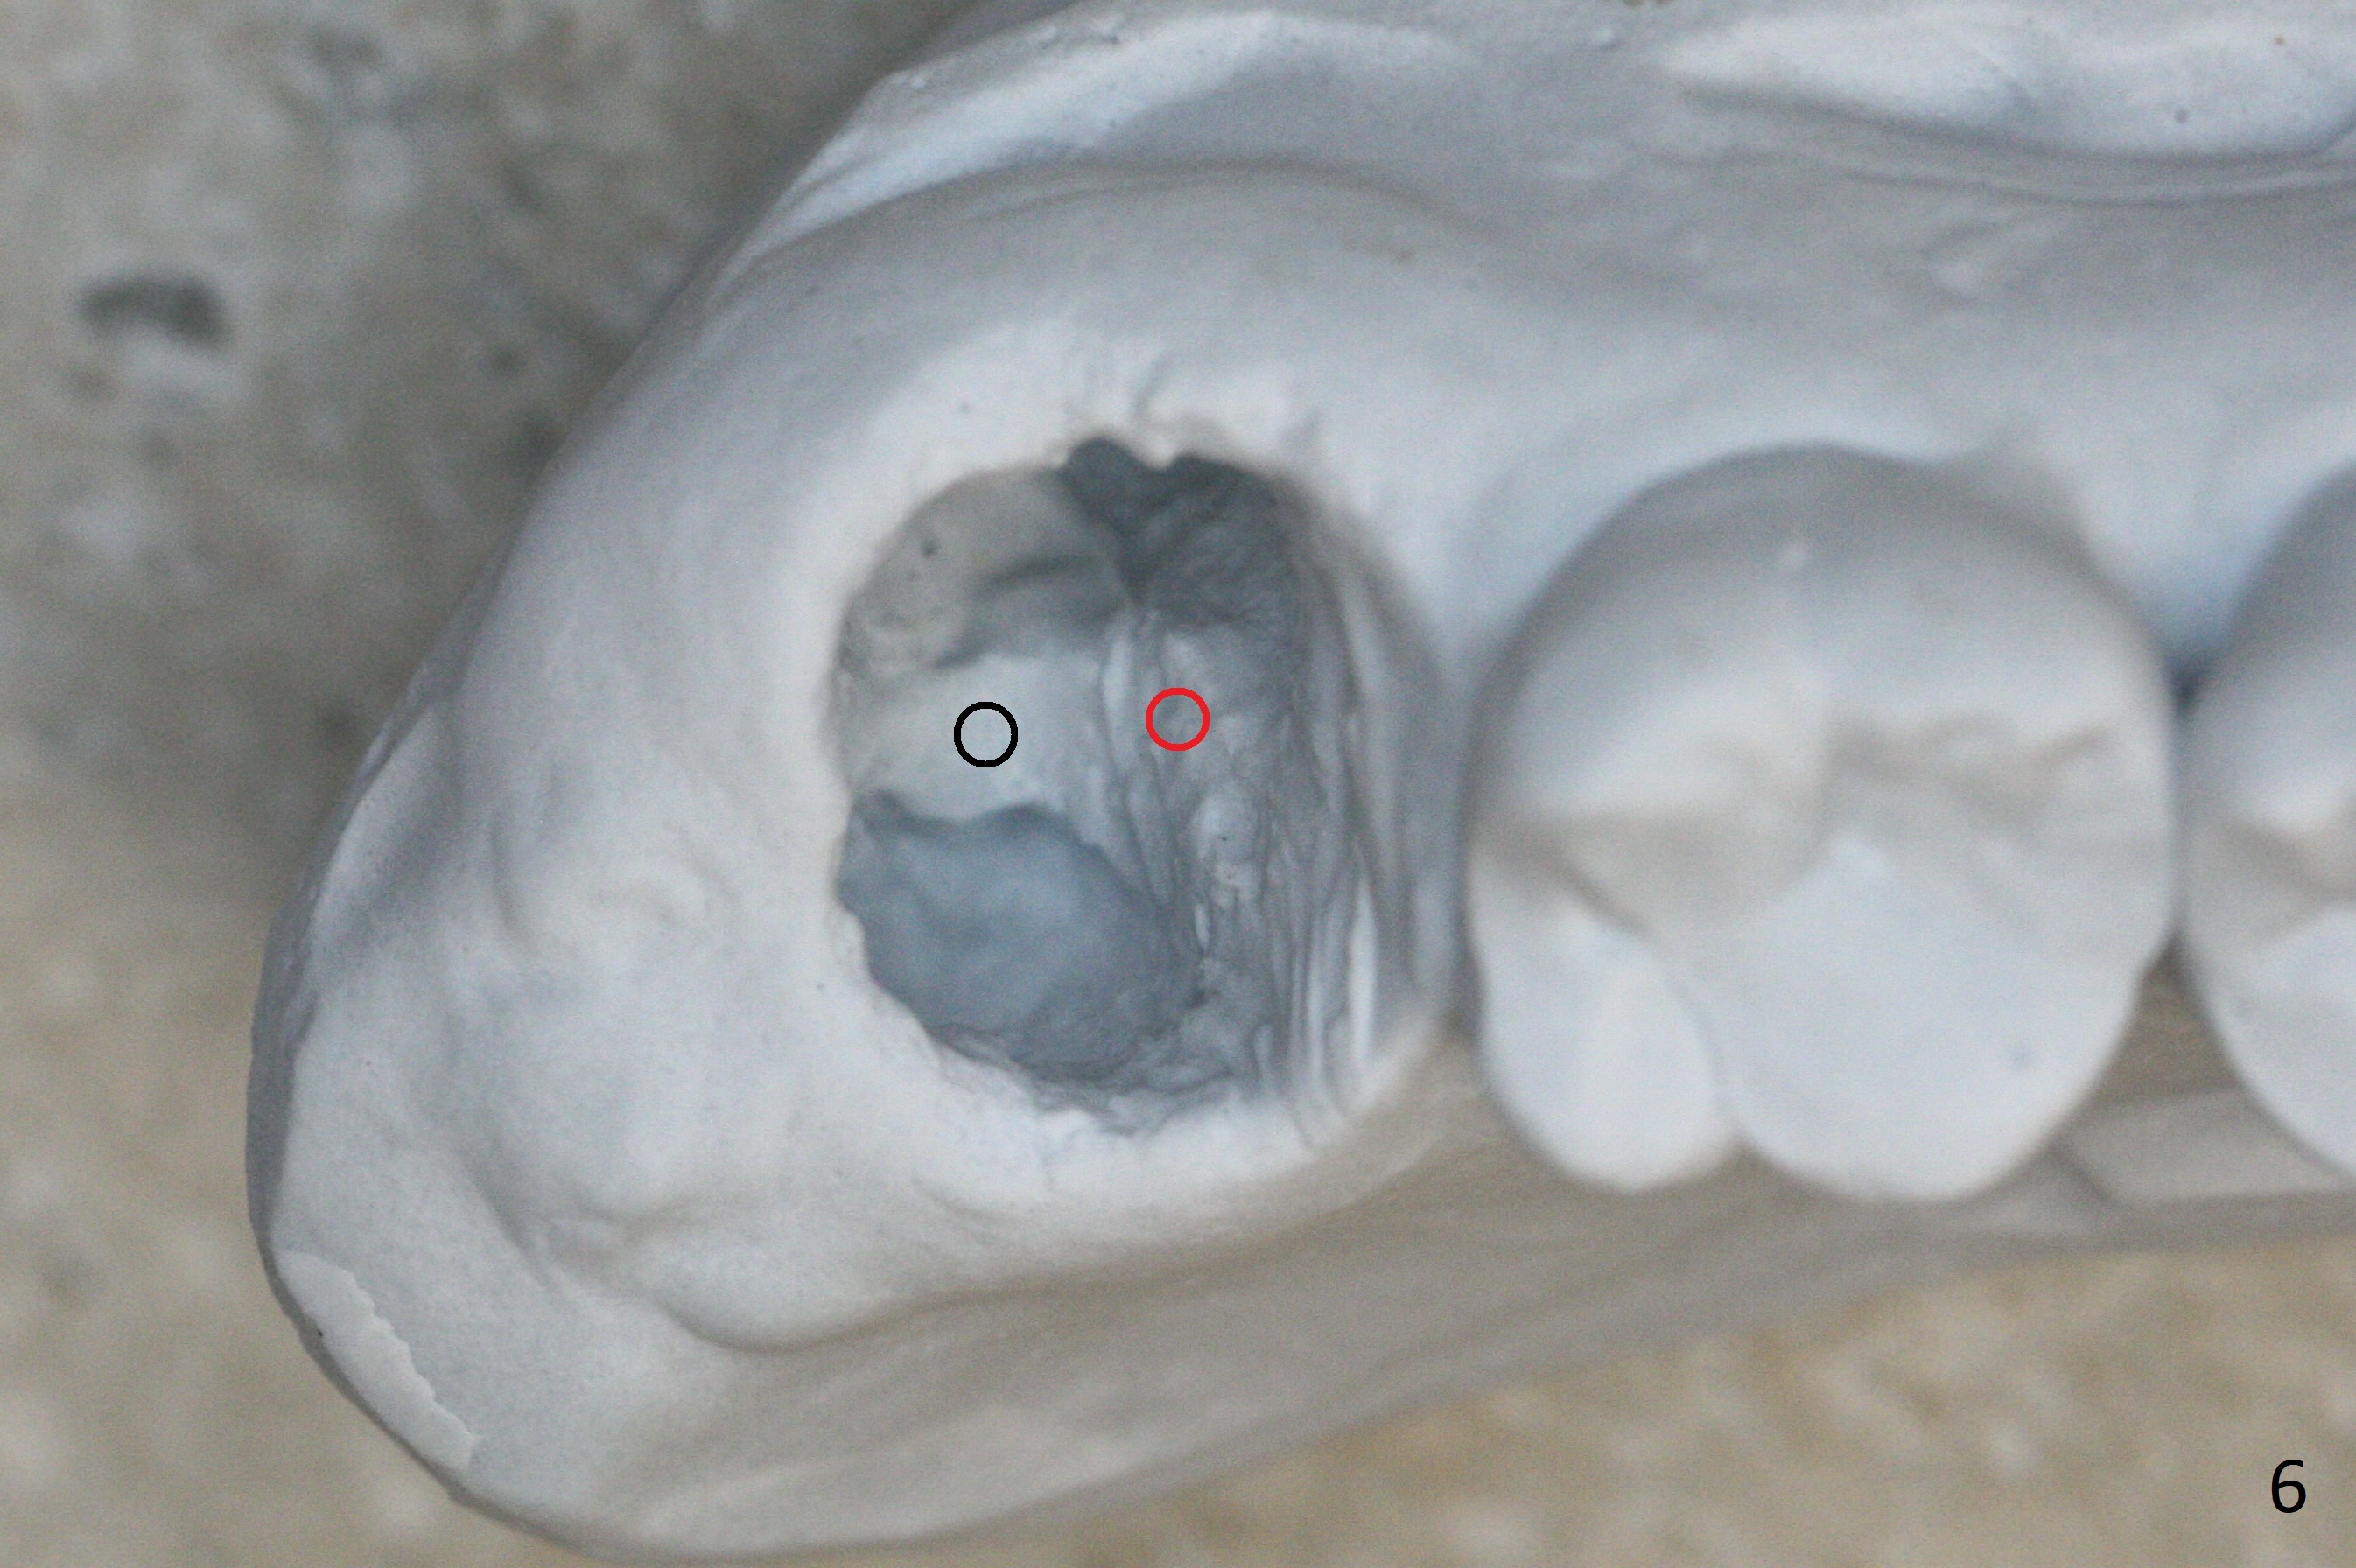

There is a fistula distal to the tooth #2 with deep pocket distopalatally (Fig.1 *), corresponding to palatal root fracture (Fig.2). There is a septum (Fig.3 S) between the buccal (B) and palatal (P) sockets. Osteotomy is initiated in the center of the septum (Fig.4 black circle). In fact the center of the socket is buccal (red circle), in which osteotomy should have been established because of the presence of the distopalatal bony defect associated with the root fracture and the distal fistula. The less ideal initial osteotomy leads to palatal placement of the implant and abutment (Fig.11 vs. 12).

Fig.5 shows the mesial slope of the socket (M), which is more or less the center of the socket mesiodistally. If the osteotomy were set up in the red circle (Fig.6) in the mesial slope (Fig.8 green dashed line), the trajectory of 4.5x11 mm dummy implant (Fig.7) would be more ideal (Fig.8 red outline) with more native bone contact. Finally a longer IBS implant is placed (4.5x15 mm, Fig.9,10) to achieve primary stability (50 Ncm). When the provisional is removed for impression 3 months 10 days postop, the implant is found to have been placed distopalatally (Fig.13), which should have been avoided. It appears essential to use guide for a distal implant. It is agonizing to re-encounter the off-axial implant (Fig.14) and the distopalatal access hole (Fig.15) 1 year post cementation. It is also amazing that the abutment screw has not loosened. A fair-sized piece of bone graft has just been removed buccally (Fig.15,16). The patient complains of sensitivity 2 years 3 months post cementation, although there is no abnormality around the implant crown. Guided surgery is essential to avoid restoration complication. There is no thread exposure nearly 3 years post cementation; in fact the apical portion of the abutment is covered by the bone (Fig.17,18).